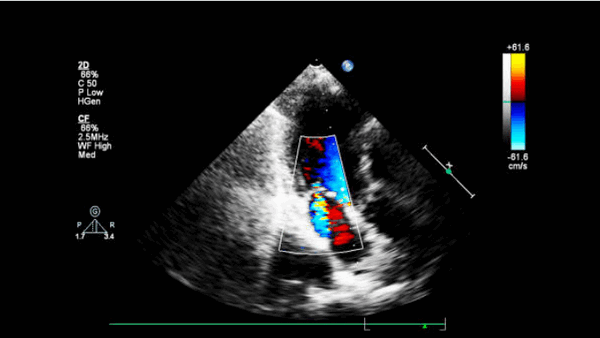

- Острая МН. Это может быть связано с дисфункцией или разрывом сосочковых мышц или разрывом хорды, что может быть определено с помощью 2-D эхокардиографии. Там может быть надрыв сосочковой мышцы или хорды, а струю митральной недостаточности можно увидеть на непрерывном волновом или цветном доплеровском картировании потока.

Ишемическая регургитация митрального клапана и разрыв папиллярных мышц

- Частота возникновения ишемической митральной регургитации (МР) у пациентов после ИМ составляет приблизительно 20%, аналогична при переднем и нижнем инфаркте и чаще всего бывает легкой или средней степени тяжести, но связана с повышенным кратковременным и долгосрочным смертность.

- При нижнем инфаркте миокарда ишемическая или инфарктированная заднемедиальная папиллярная мышца вызывает отсутствие и снижение подвижности медиальной половины, преимущественно задней створки митрального клапана, что приводит к неправильной адаптации створки, относительному западению передней створки или псевдопролапсу и эксцентрической направленной заднелатерально струе митральной недостаточности.

- При переднем инфаркте миокарда дилатация и дисфункция левого желудочка приводят к нисходящему и латеральному смещению обеих папиллярных мышц, неполной, но симметричной дислокации створок и центральной митральной регургитации на эхокардиографии.

- Когда разрыв папиллярной мышцы является частичным, на эхокардиографии может быть продемонстрировано западение одной или обоих митральных створок. После полного разрыва папиллярных мышц МР становится тяжелой, и вовлеченный митральный клапан с частью его папиллярной мышцы становится отслоенным или свободно выпадает в левое предсердие.

- Tрансторакальная эхокардиография недооценивает тяжесть эксцентричных струй митральной регургитации, следовательно, чреспищеводное исследование является тестом выбора, если клинически или обычная эхокардиограмма подозревают значительную МР.